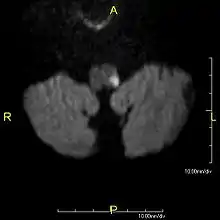

Clinical B1000 diffusion weighted MRI image showing an acute left sided dorsal lateral medullary infarct- Abnormal head impulse test, one directional nystagmus, and abnormal skew due to a central vertigo, specifically Wallenberg syndrome